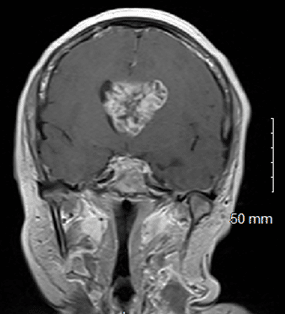

Neurology | Mar 12, 2025

Lateral Intraventricular Glioblastoma Presentation with Increased Survival Rate

Background: Although glioblastoma is the most common malignant primary brain tumor, it rarely presents in the intraventricular region(s) of the...Read More